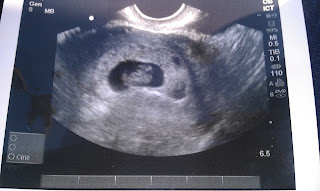

This pregnancy has been very different from my first. The morning sickness in the first trimester was terrible! I had to drink lots of water to keep from being hungry and dehydrated. I never knew what I was going to be able to eat from moment to moment. All meat was disgusting!!! On top of the morning sickness I got the flu which left me throwing up so much I was in tears. Then I got a cold that would not go away. I was never so happy to say goodbye to my first trimester. In my second trimester I soon was able to eat chicken followed by ham but no other meat. My poor husband is eating a lot of chicken. I am carrying this baby a lot different, and have a lot of headaches. On 12/12/12 John, LeAnne & and I eagerly went to my 21 week ultrasound appointment. It was adorable to have LeAnne at my head watching the ultrasound and too cute when she said they're is the baby's heartbeat. Little one was being a turkey during the ultrasound, very active which made the ultrasound technicians job interesting. After seeing the important anatomy she told us "It's a little man"! Were having a boy! I was in shock and the first words out of LeAnne's mouth was "but I wanted a sister". Seeing our boy move around inside and hearing he is developing wonderfully was awesome!! After our appointment we enjoyed spreading the news to family and friends! Then came the fun looking at boys clothes and figuring out how to design his nursery. I was excited when John said "you decorated LeAnne's nursery now its my turn to decorate Christian's nursery". It looks like he will have a Disney Cars nursery with some tools and some WSU cougar decor too. LeAnne is warming up to the idea of having a brother. She has asked if she can give Lucky the horse to her brother and can be heard calling Christian "My boy". I loved having a little brother and I am very excited for her to have a little brother. I am feeling Christian move around a lot and LOVE it!